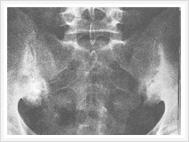

X线检查对AS的诊断有极为重要的意义,约98%~100%病例早期即有骶髂关节的X线改变,是本病诊断的重要依据。

早期X线表现为骶髂关节炎,病变一般在骶髂关节的中下部开始,为两侧性。开始多侵犯髂骨侧,进而侵犯骶骨侧。可见斑点状或块状骨侧明显。继而可侵犯整个关节,边缘呈锯齿状,软骨下有骨硬化骨质增生,关节间隙变窄。最后关节间隙消失,发生骨性强直。骶髂关节炎X线下易用按钮约诊断标准分类5级:0级为正常骶髂关节,Ⅰ级为可疑骶髂关节两侧炎;Ⅱ级为骶髂关节边缘模糊,略有硬化和微小侵蚀病变,关节腔轻度变窄;Ⅲ级为骶髂关节两侧硬化,关节边缘模糊不清,有侵蚀病变伴关节腔消失;Ⅳ级为关节完全融合或强直伴或不伴残存的硬化。

早期X线检阴性时,可行放射线核素扫描,计算机断层和核磁共振检查,以发现早期对称性骶髂关节病变。但必须指出,一般简便的后前位X线片足可诊断本病。 AS的诊断标准现仍沿用1966年纽约标准,或1984年修订的纽约标准,条件如下: